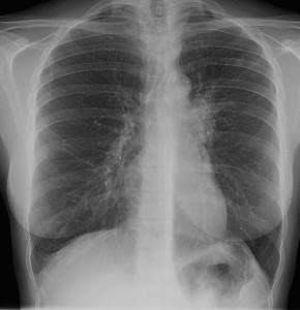

Old TB + right pneumonia ; aortic arch aneurysm